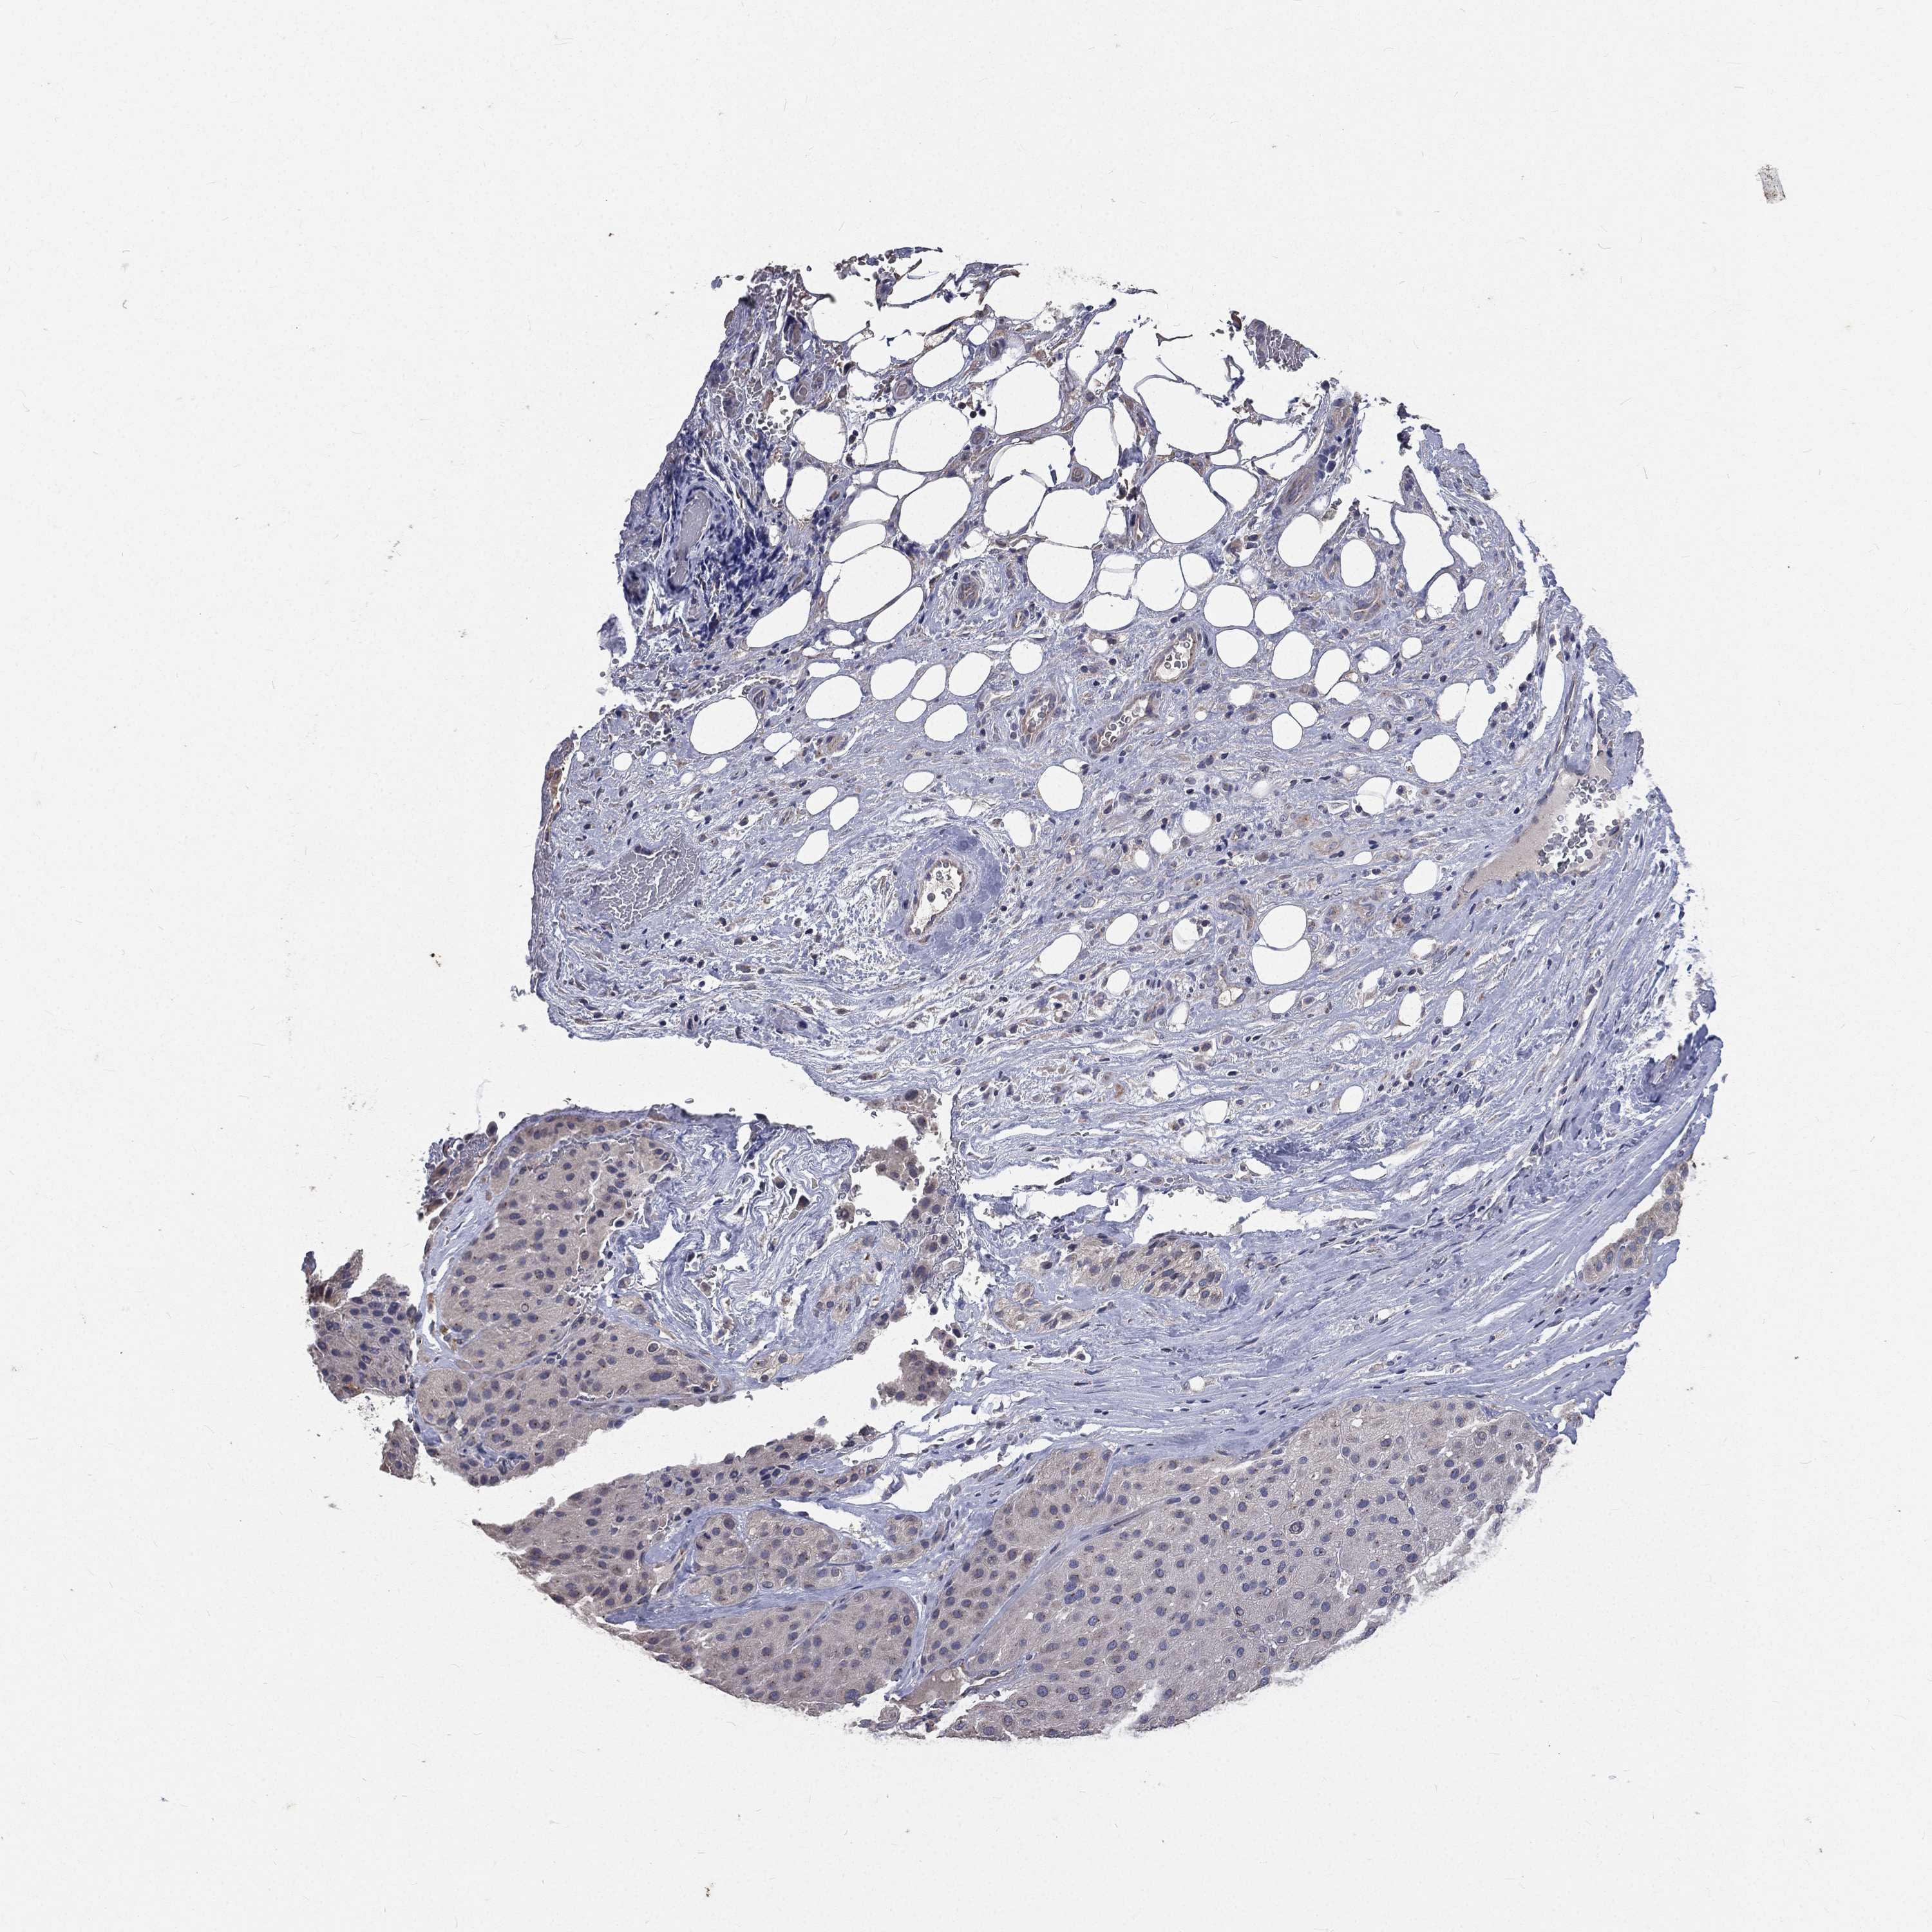

MELANOMA - Protein expressioni

A mouse-over function shows sample information and annotation data. Click on an image to view it in a full screen mode. Samples can be filtered based on level of antibody staining by selecting one or several of the following categories: high, medium, low and not detected. The assay and annotation is described here.

Note that samples used for immunohistochemistry by the Human Protein Atlas do not correspond to samples in the TCGA dataset.

Antibody stainingi

Antibody staining in the annotated cell types in the current human tissue is reported as not detected, low, medium, or high, based on conventional immunohistochemistry profiling in selected tissues. This score is based on the combination of the staining intensity and fraction of stained cells.

Each image is clickable and will lead to virtual microscopy that enables deeper exploration of all samples and also displays staining intensity scores, fraction scores and subcellular localization as well as patient and tissue information for each sample.

Antibody HPA021191

Antibody HPA021762

Malignant melanoma, NOS

Malignant melanoma, Metastatic site